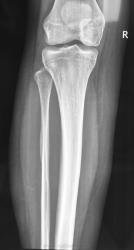

Девочка 17 лет. Беспокоят боли в в/3 голени несколько месяцев, преимущественно днём, Ночных болей нет. Клинически - некоторая болезненность при пальпации в/з правой голени по латеральной стороне. Консультировалась в частном порядке в одном из институтов радиологии. Рентгенолог по данным снимкам поставил диагноз - саркома (!) малоберцовой кости. Направлена для лечения к нам в больницу. Представлены рентгенограммы с динамикой процесса 1 месяц.

Мы убедительных данных за злокачественное образование не видим. Хотелось бы узнать мнение уважаемых коллег.

Сегодня взяли открытую биопсию.

жаль - поторопились, потому что если это остеоид-остеома и "гнездо" не попадет в биоптат, то дигноз не поставят, а болячка останется

На мой взгляд, вероятность остеоид-остеомы мала, все же гнездо должно быть более округлым, а здесь больше линейное просветление. У нас таких было много, сейчас вспомнила, и в малоберцовке тоже было,  пытались томографировать, когда КТ еще не было.

Ольга, я не линейное просветление имела в виду, а кнаружи от него очень мелкое уплотнение с ободком просветления по периферии. Без КТ его вряд ли удастся вывести, но теперь не узнаем...